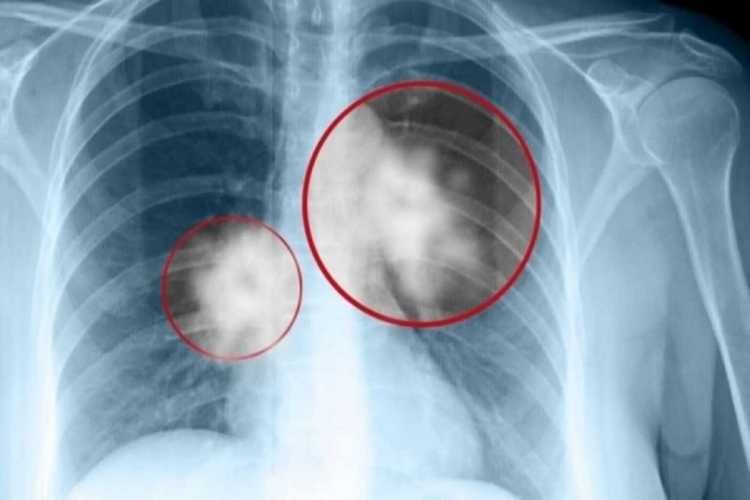

Όλα όσα πρέπει να ξέρουμε για την υγεία των πνευμόνων, της καρδιάς και το ηλεκτρονικό τσι